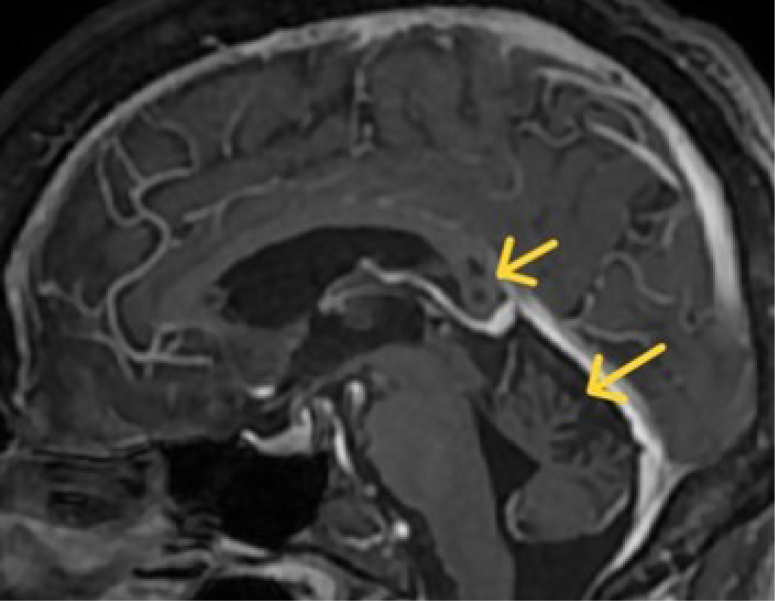

Co-occurrence of radiological signs of Marchiafava-Bignami disease and alcohol-related cerebellar degeneration.

Marchiafava-Bignami病和酒精相关性小脑变性的影像学征象共同出现。